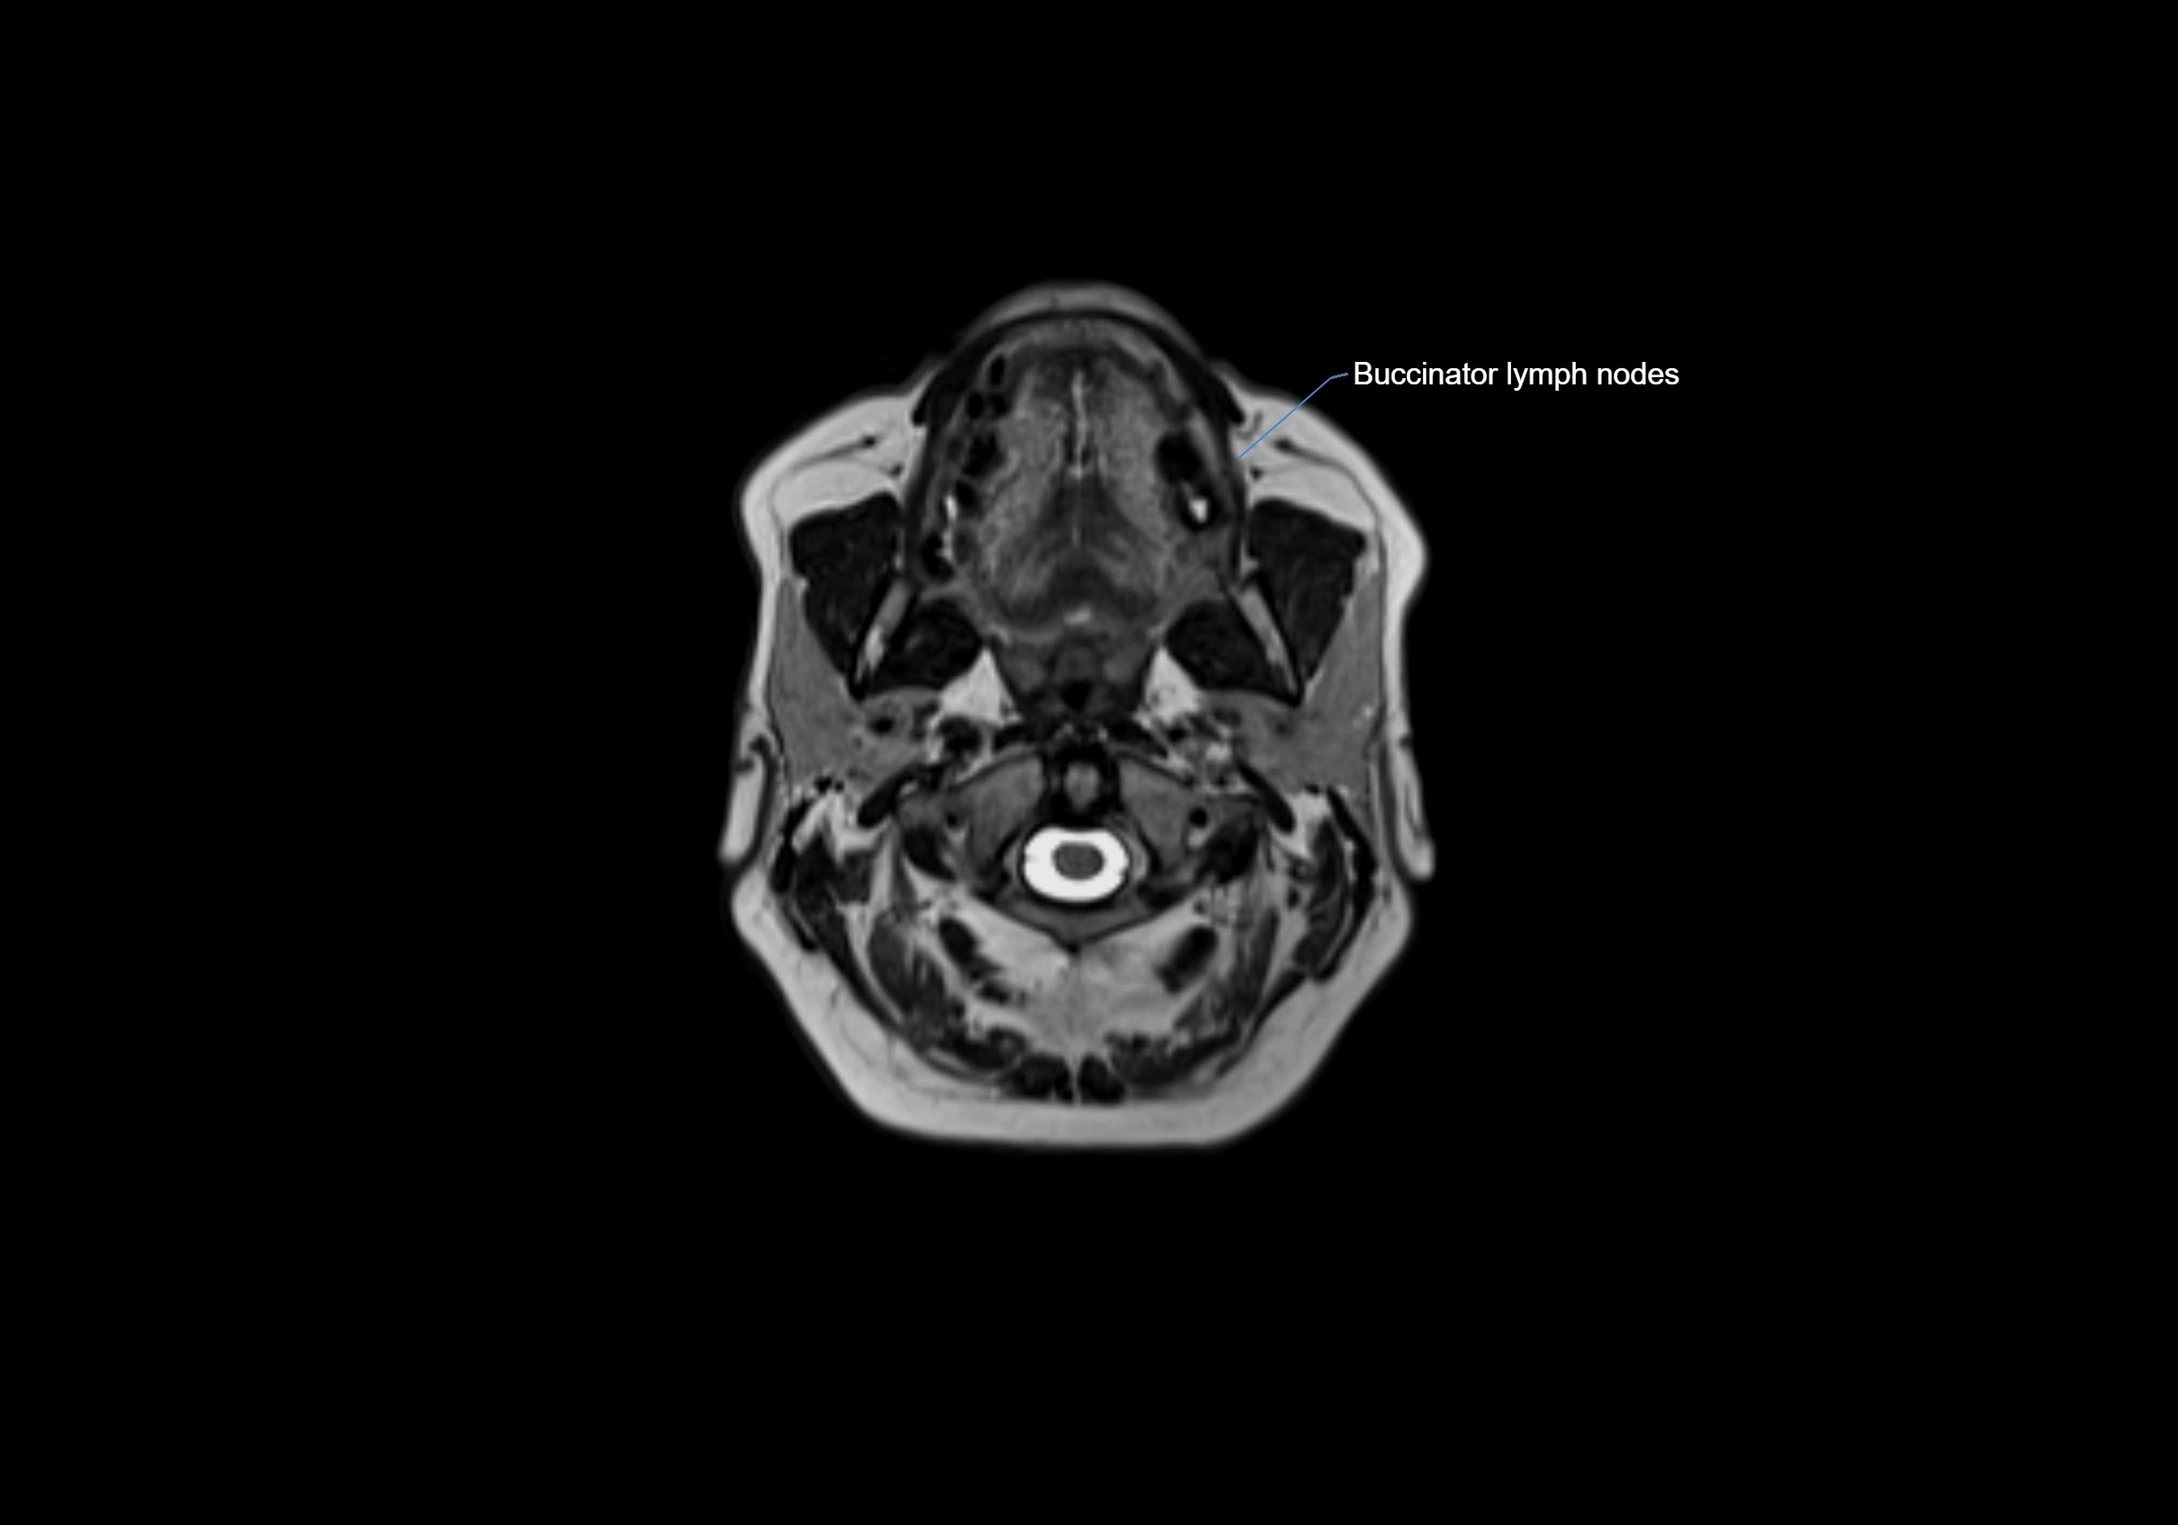

MRI Appearance

T1-weighted images:

• Normal accessory nodes appear as small, oval hypointense to intermediate signal structures within subcutaneous fat

• Surrounded by hyperintense fat, enhancing contrast for visualization

• Pathological nodes may appear enlarged or rounded, sometimes with cortical thickening

MRI images